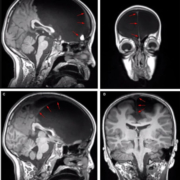

https://adolfogarcia.com.ar/wp-content/uploads/2020/10/Bachli-et-al.-2020.-Reliability-neurocognitive-markers-NeuroImage-scaled.jpg10381920Adolfo Garciahttps://adolfogarcia.com.ar/wp-content/uploads/2020/07/logoadolfo.pngAdolfo Garcia2020-10-15 17:18:022022-07-19 11:58:45Evaluating the reliability of neurocognitive biomarkers of neurodegenerative diseases across countries: A machine learning approach | NeuroImage